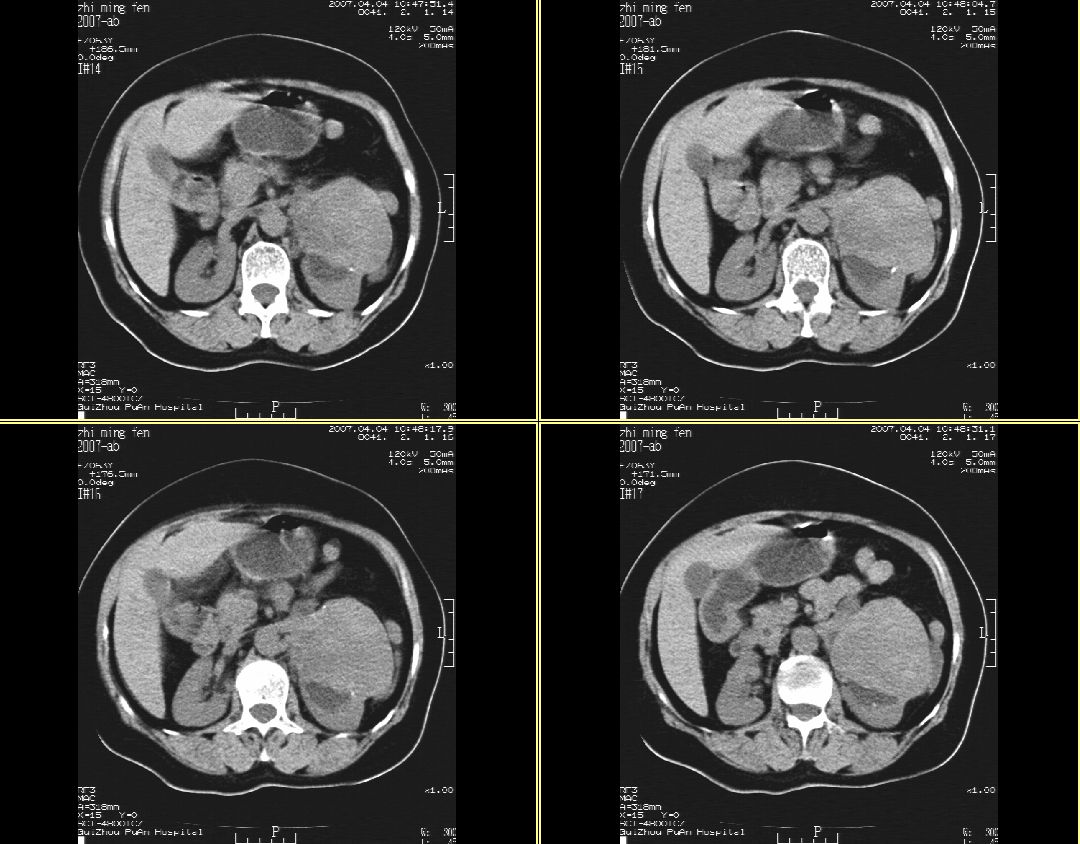

以下是引用hhcckk在2007-4-9 9:18:00的发言:[br]我认为就是一个病灶,病灶上端密度较均匀,下方有明显的钙化,部分呈不完全的环状,考虑肾癌[br]1、肾癌的特征性ct表现为肾实质的占位,局部隆起外突[br]2、肿瘤内的钙化常见,多发生在肿瘤内部,也可以在肿瘤周边呈弧型或不完全的环行钙化[br]3、最常见的三大症状,血尿,腰痛,包块此病人也较符合,增强吧

以下是引用swyyy2007在2007-4-9 18:42:00的发言:[br]支持左肾癌累及肾窦肾盂,左肾积水 [br] [br]